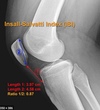

imaging for patellar tendon rupture: Insall salvation ratio > Blackburn-peel ration > caton-dechamps ration > ## Footnote "BIC 1,2,3"

Blackburne-Peel ratio > 1.0 Insall-Salvati ratio is > 1.2 Caton Deschamps ratio > 1.3 ## Footnote Insall-Salvati ratio is > 1.2, normal between 0.8 and 1.2 Blackburne-Peel ratio > 1.0 normal between 0.5 and 1.0 Caton Deschamps ratio > 1.3 normal between 0.6 and 1.3